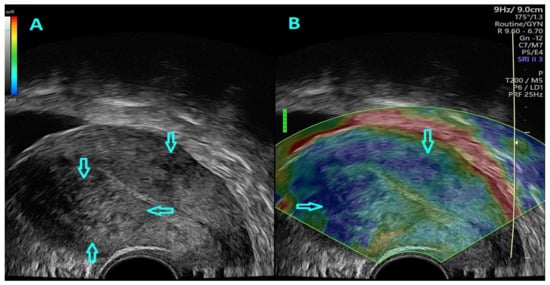

2.4. Strain Ratio Elastography Evaluation

- Săsăran, V.; Turdean, S.; Gliga, M.; Ilyes, L.; Grama, O.; Muntean, M.; Pușcașiu, L. Value of Strain-Ratio Elastography in the Diagnosis and Differentiation of Uterine Fibroids and Adenomyosis. J. Pers. Med. 2021, 11, 824. [Google Scholar] [CrossRef]